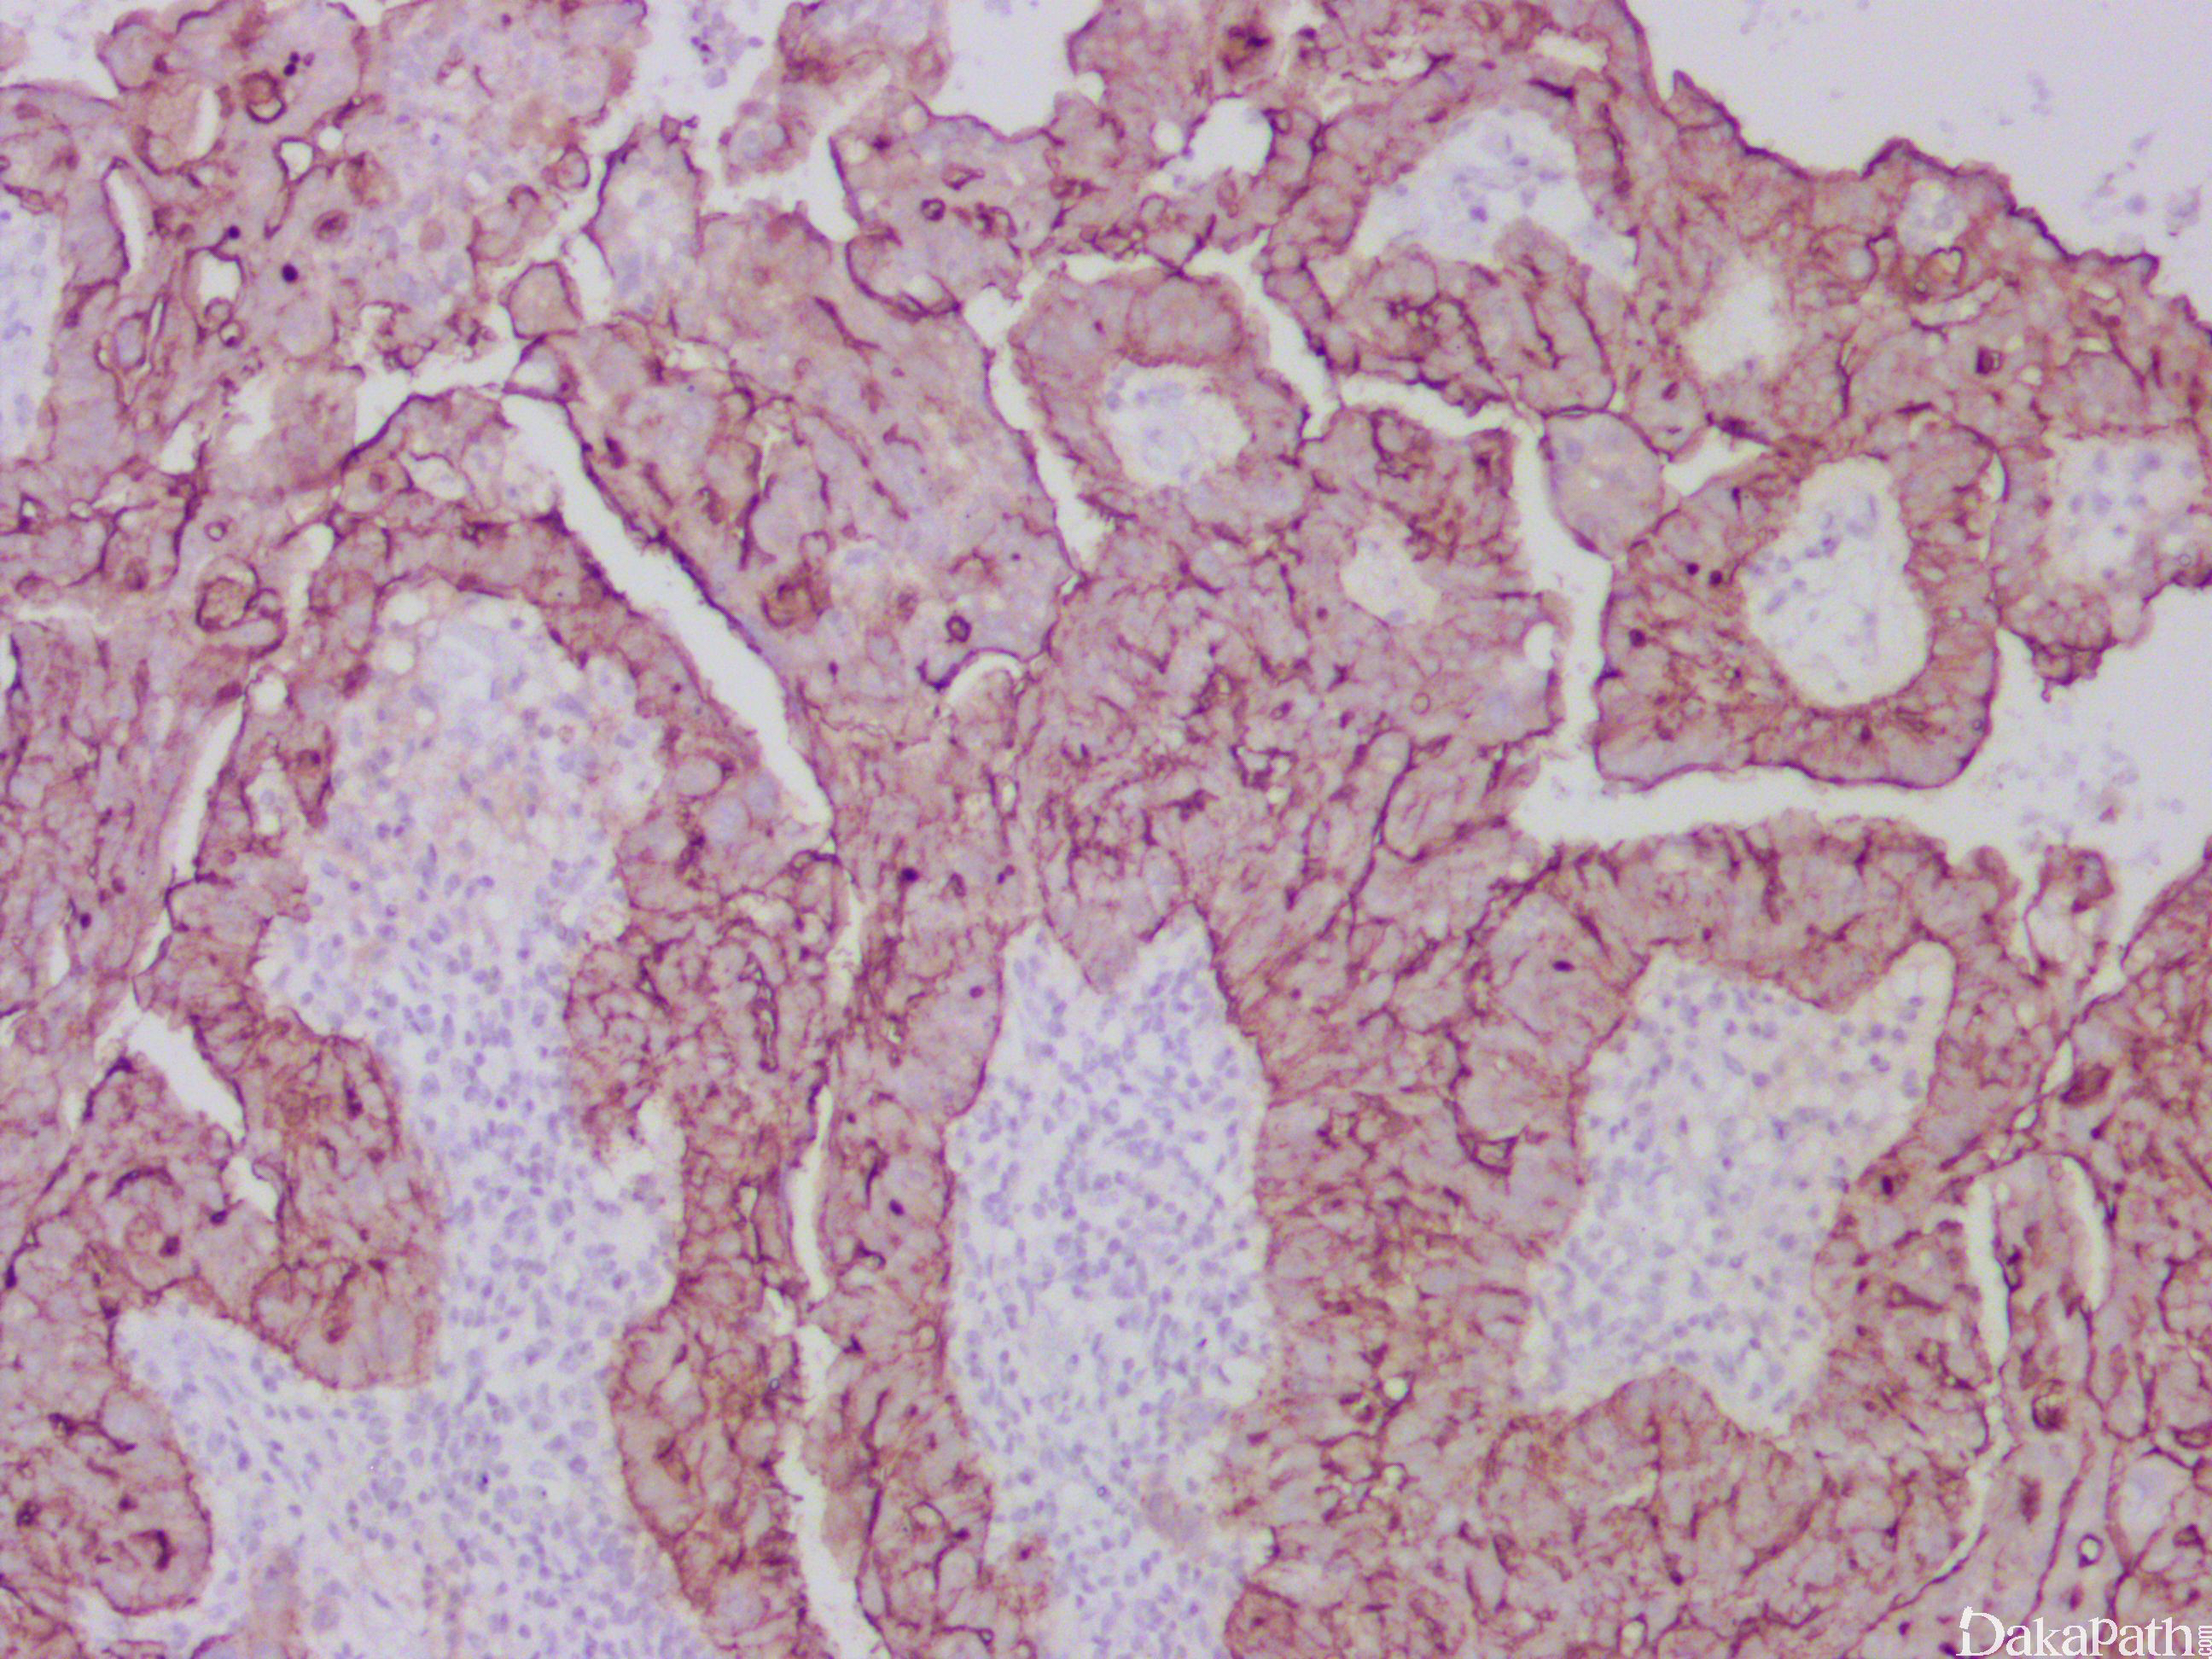

- 罕见,形态学类似卵巢浆液性癌;

- 多房囊性或囊实性肿瘤,特征性改变是被覆浆液性上皮的乳头状结构呈浸润性生长,间质伴促结缔组织增生,也可见单个细胞浸润;

- 常伴有交界性浆液性肿瘤成分。

PAX8,CA125,WT1 和 ER、BerEP4. Leu-M1 阳性,calretinin、HBME1 阴性。